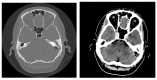

Background: This study presents a comprehensive analysis of cholesteatoma of the middle ear, focusing on its clinical presentation, diagnostic imaging, and treatment outcomes. Cholesteatomas are defined by the keratinized squamous epithelium within the middle ear, leading to significant bone erosion, often affecting the ossicular chain and surrounding structures. Methods: The study explores various mechanisms involved in cholesteatoma progression, including enzymatic lysis, inflammatory responses, and neurotrophic disturbances. The study conducted a retrospective clinical and statistical review of 580 patients over a 20-year period (2003-2023), highlighting the role of advanced imaging, including computed tomography (CT) and diffusion-weighted magnetic resonance imaging (DWI), in preoperative planning and postoperative follow-up. Results: Findings revealed that early detection and intervention are crucial in preventing severe complications such as intracranial infection and hearing loss. Surgical treatment primarily involved tympanoplasty and mastoidectomy, with a recurrence rate of 1.55% within two years. The study underscores the importance of integrating imaging advancements into clinical decision-making to enhance patient outcomes and suggests further investigation into molecular mechanisms underlying cholesteatoma progression and recurrence. Histopathological and microbiological analysis was performed to identify pathological patterns and microbial agents. Conclusions: The study highlights the importance of early diagnosis and intervention to prevent complications such as intracranial infections and permanent hearing loss, while also emphasizing the role of advanced imaging techniques in the management and long-term monitoring of cholesteatoma patients.